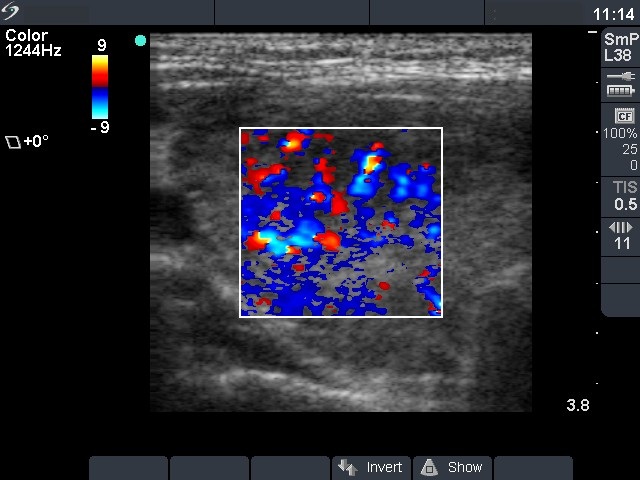

Right lobe, horizontal view

Right lobe, transverse scan, color Doppler mode. The vascularization is increased.